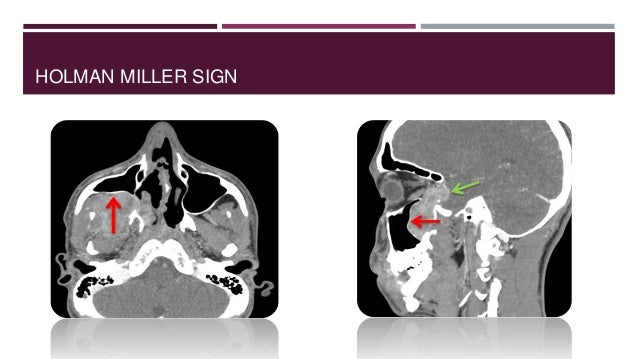

6. 6. SITE OF ORIGIN  Most common site - Superior Margin Of Sphenopalatine Foramen  Pterygoid wedge  Vidians canal  Basisphenoid

17. 17. HOLMAN MILLER SIGN